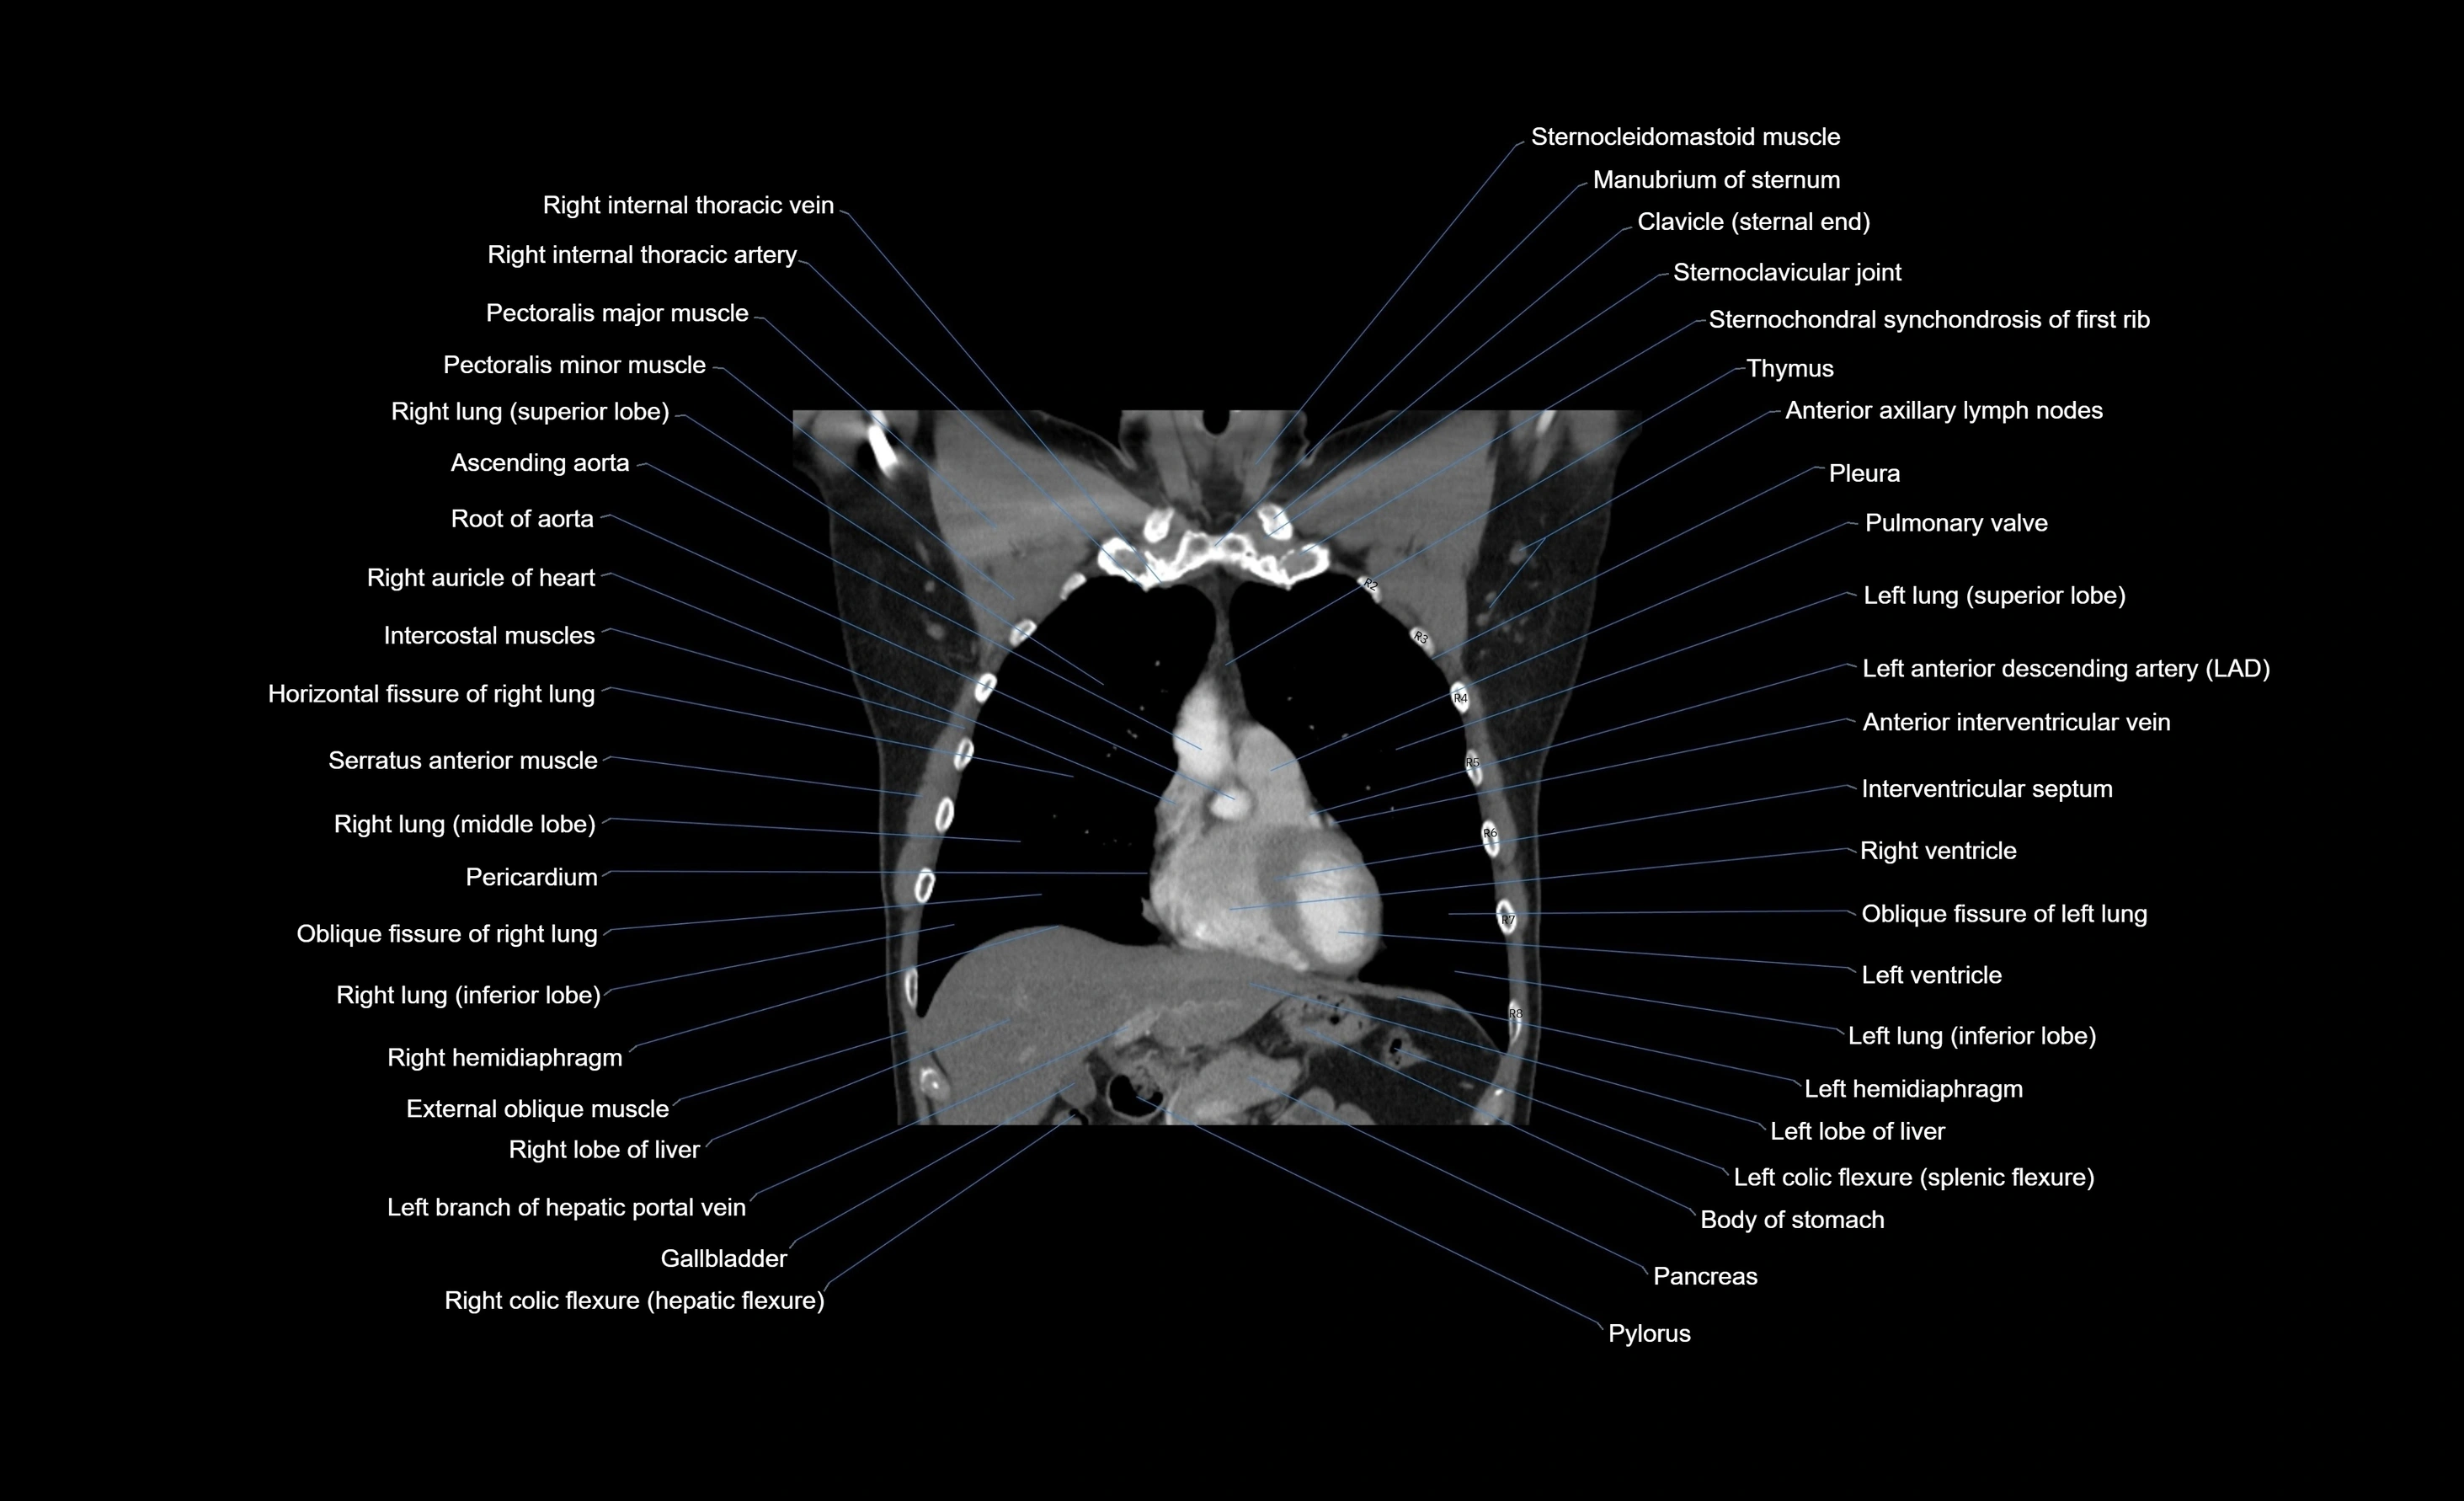

CT images